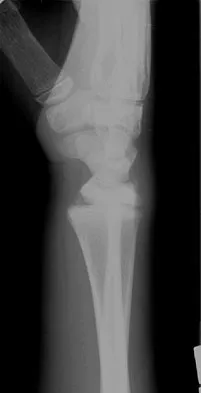

Examination of an obese 3-year-old girl reveals 30 degrees of unilateral genu varum. A radiograph of the involved leg with the patella forward is shown in Figure 10. Management should consist of

Explanation

The clinical scenario describes infantile tibia vara (Blount's disease). The radiograph shows severe deformity with the characteristic Langenskiold stage 3 changes of the medial proximal tibial metaphysis that distinguish it from physiologic bowing. The preferred treatment is proximal tibiofibular osteotomy with acute correction into slight valgus to unload the damaged area of the physis. This method provides the best results in patients younger than age 4 years. Continued observation would result in progressive deformity. Bracing is most effective in younger children with less severe deformity. Lateral proximal tibial hemiepiphysiodesis relies on growth of the injured medial physis for correction and would result in severe tibial shortening in this young child. Complete epiphysiodesis also produces severe shortening and requires multiple lengthening procedures. Johnston CE II: Infantile tibia vara. Clin Orthop 1990;255:13-23.